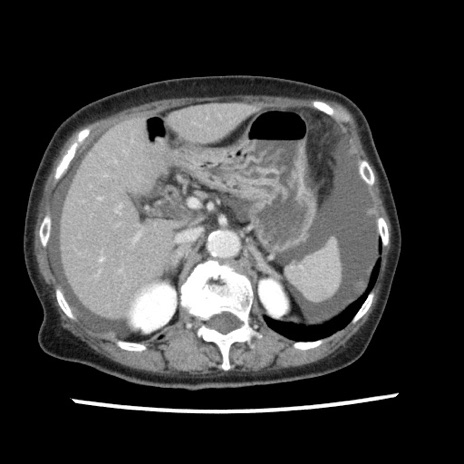

症例1(横断像)

【症例】80歳代女性

【主訴】腹痛

【現病歴】8時間前から腹痛あり来院。

【既往歴】糖尿病、脂質異常症、子宮体癌にて子宮全摘術

【身体所見】意識清明・会話良好だが腹痛で苦悶様、全腹部にわたって反跳痛と圧痛あり

【データ】WBC 13600、CRP 0.14、LDH 224、CK 90